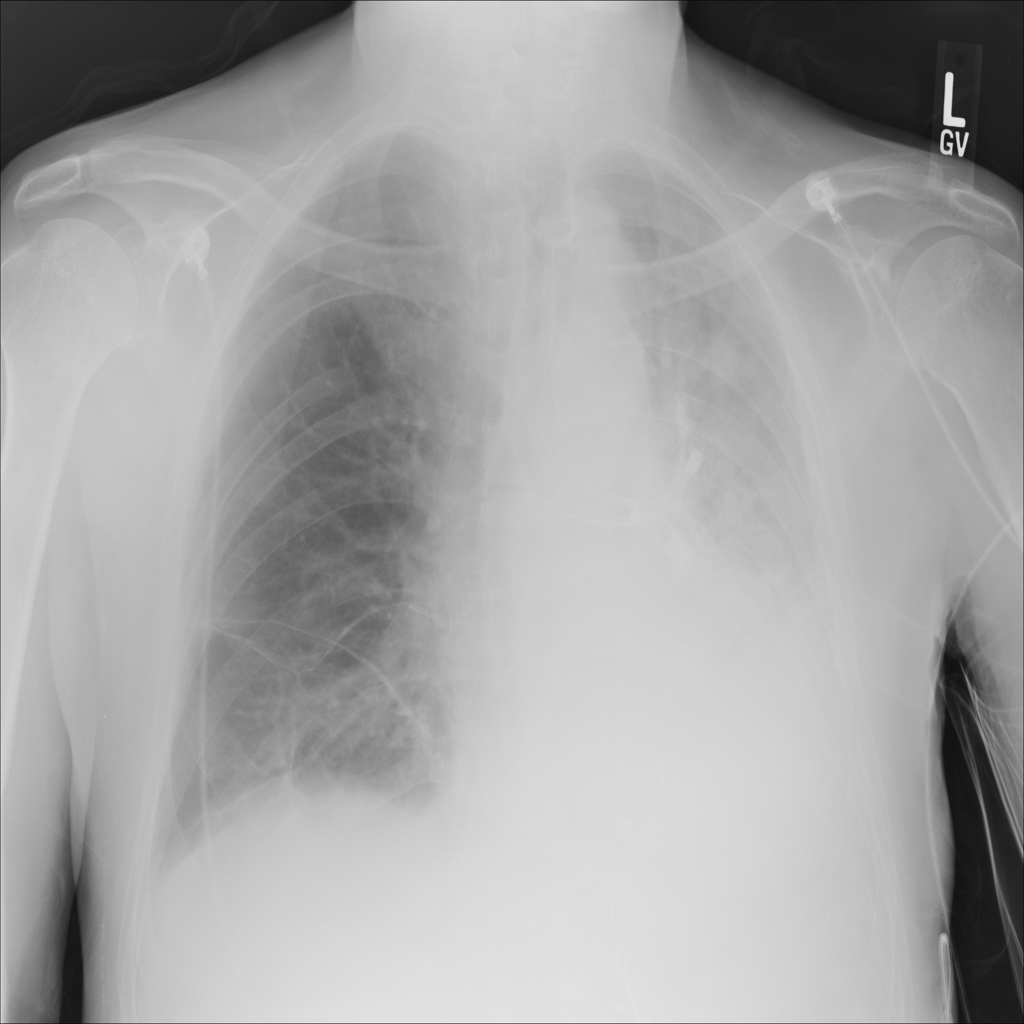

PAT-B733 · IMG-000Consolidation

PAT-B733 · IMG-000

PA